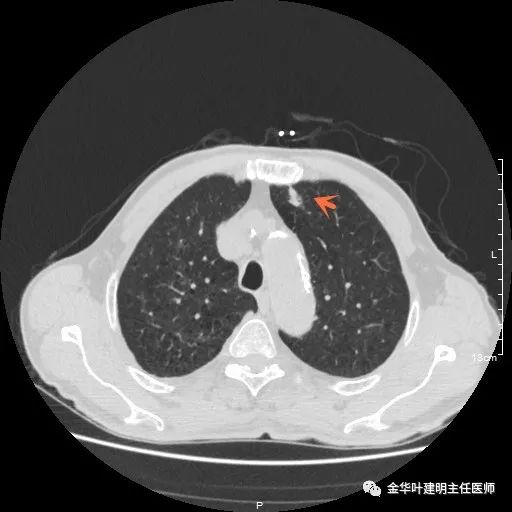

以上示右上病灶,我们称其病灶1。为囊腔型病灶,边缘为磨玻璃影,且轮廓清楚,局部有点状高密度,需考虑为囊腔型肺癌。单纯从单一病灶来看,这样的年纪可以随访或局部切除。